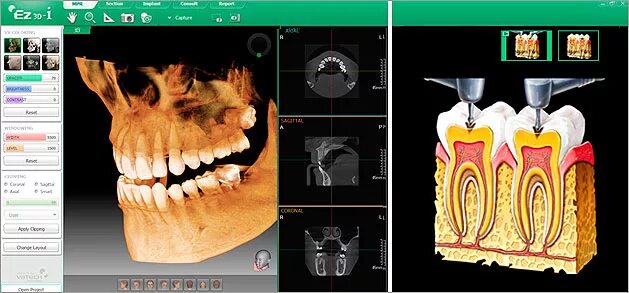

Picasso кт